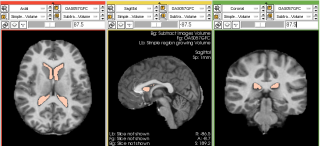

The Brain Volume Refinement (BVeR) extension is designed to assist neuroscience studies. The BVeR algorithm is suitable for a broad use of healthy brain structural MRI images, e.g. T1w and T2w, offering broad application in many large data analyses. The main contribution of the proposed method is related to the reduction of manual interference in the brain volume refinement after an automatic skull stripping procedure been performed, helping to reduce human errors and processing time. Even though the BVeR method does not provide a fully brain extraction algorithm, it can be helpful as a ad hoc image processing step in which increase the quality of well-known brain extraction algorithm in the literature. Any brain extracting frameworks can be refined with this method, e.g. FSL-BET, FreeSurfer, BEasT, 3DSkullStrip, ROBEX, OptiBET and many others.